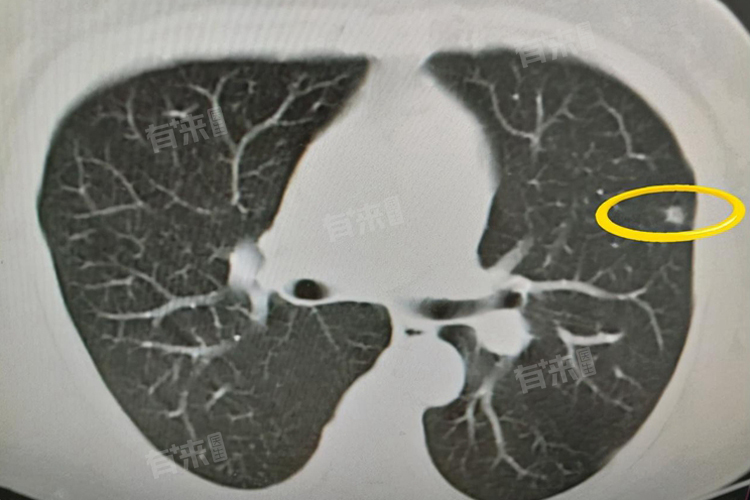

肺GGO即肺部磨玻璃影,指在胸部CT影像上,呈现出的云雾状淡薄影或圆形结节,样子类似磨砂玻璃,其密度介于正常肺组织与实性病变之间,能隐约看到其中走行的血管和支气管影。其并非一种疾病的特定诊断,而是一种影像学表现。

1、薄层胸部CT:通过薄层扫描技术,能更清晰、准确地显示肺GGO的形态、密度、边缘等特征,对微小病灶的检出和性质判断有重要价值。